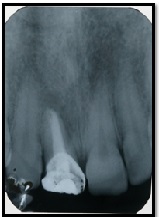

Management of a Dentigerous Cyst Associated with Mesiodens: A Case Report

Harsimranjit Kaur*,Sonam Mahajan, Pratibha Marya, Roma Goyal, Pratima Sharma, Harshita